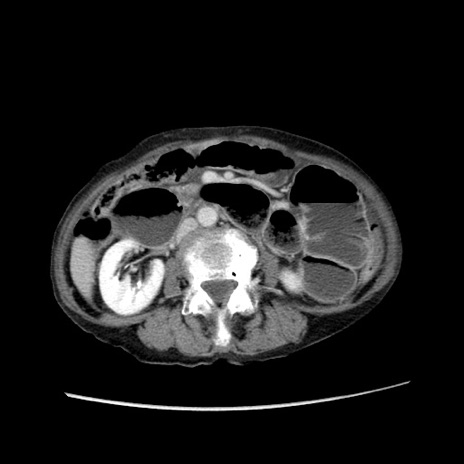

症例25(横断像)

【症例】80歳代女性

【主訴】胸のつかえ感

【現病歴】約9時間前に食後から胸のつかえた感じあり、嘔吐あり、来院。

【既往歴】胃癌(全摘)、胆摘、虫垂炎

【身体所見】心窩部に圧痛あり、反跳痛なし。

【データ】WBC 5700、CRP 0.05